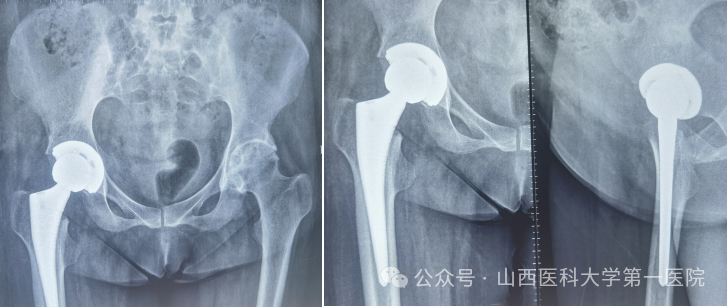

针对患者复杂病情,科室组织多学科讨论。为实现从“站坐难安”到“稳步前行”,杨自权主任团队决定先为患者实施“右侧人工全髋关节置换术”。术中,团队凭借精湛技术,精准处理强直融合的关节结构,在保护周围神经血管的同时,成功植入新的人工关节假体。

强直性脊柱炎伴髋关节病变的置换手术,被誉为骨科领域的“硬仗”。杨自权总结此类患者三大诊疗难点:一是麻醉困难,患者脊柱强直,常无法配合常规麻醉体位;二是解剖变异,长期炎症导致关节周围骨质疏松、肌肉萎缩,手术视野不清,风险极高;三是对手术精度要求更高,假体安放的位置、角度稍有偏差,就会影响术后关节稳定性及使用寿命。